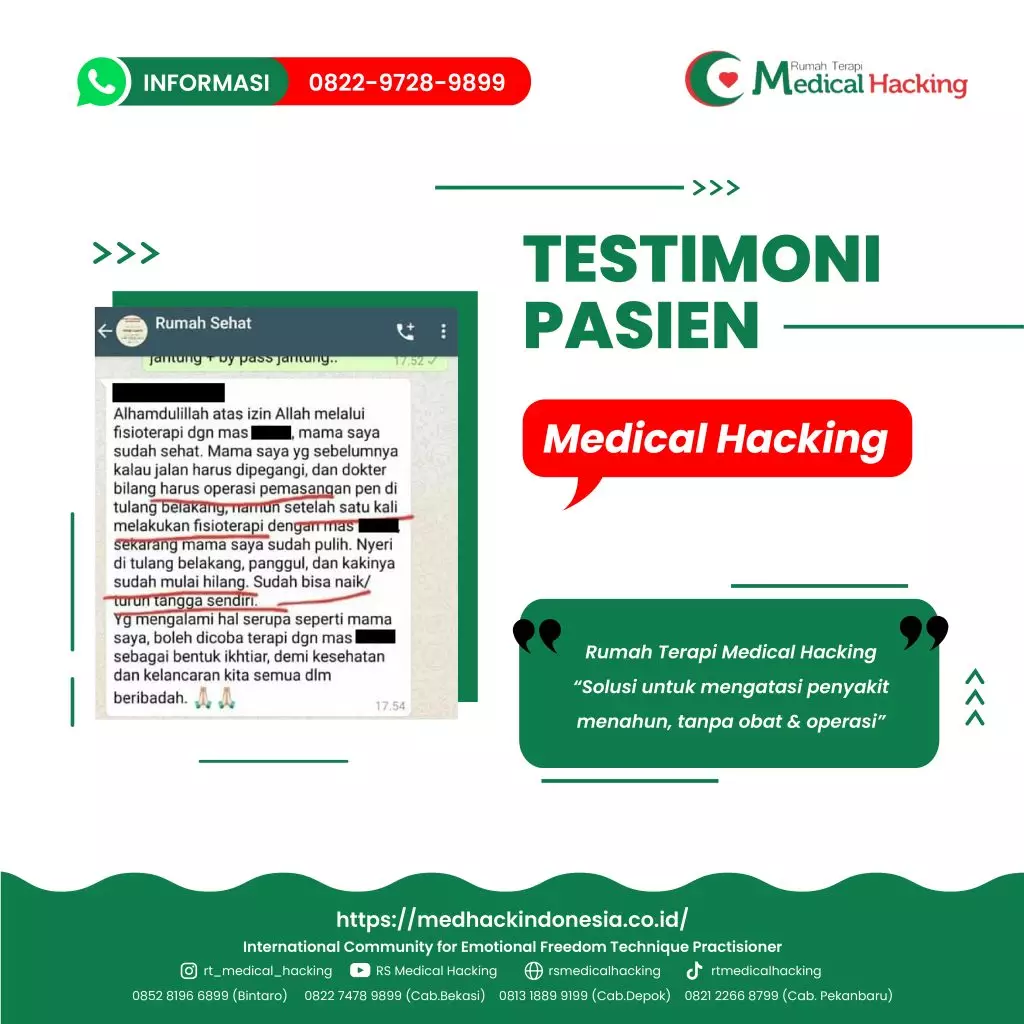

Kalau kamu pengen cara yang lebih efektif, kamu bisa cari terapi khusus yang dirancang buat ngurangin nyeri Radang Persendian secara alami. Banyak tempat terapi sekarang yang punya pendekatan modern tanpa obat kimia berat. Salah satunya adalah medicalhacking yang fokus banget bantu banyak orang ngurangin nyeri dan pulih lebih cepat lewat teknik terapi yang udah disesuaikan dengan kondisi setiap orang.

Medicalhacking juga melayani terapi stroke jakarta dengan pendekatan yang lembut tapi hasilnya nyata banget. Mereka ga cuma fokus ke satu bagian tubuh, tapi bener-bener ngeliat keseluruhan kondisi kamu biar hasil terapinya maksimal. Banyak pasien yang ngerasain tubuhnya lebih ringan, nyeri berkurang, dan gerakan jadi lebih bebas setelah dapet terapi yang konsisten.